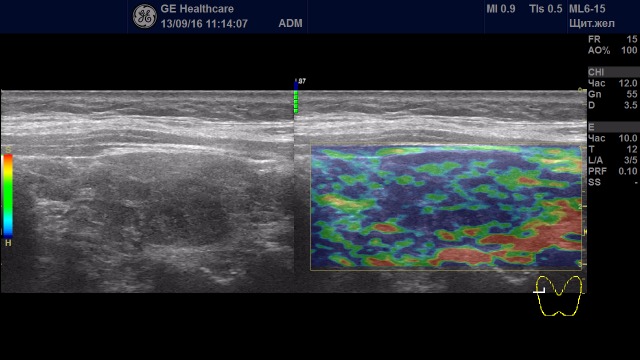

Образования с удовлетворительной эластичностью (тип I-III)